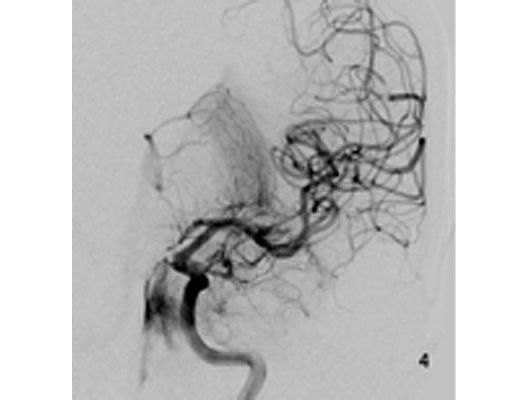

Angiographie: Behandlung von Aneurysmen

Behandlung von Aneurysmen

Aneurysmen an der Gefäßen des Gehirns können in vielen Fällen minimalinvasiv durch einen Zugang durch das Gefäßsystem, zumeist von der Leiste aus behandelt werden (sog. Endovaskuläre Therapie). Dabei gibt es z.B. die Möglichkeit ein Aneurysma durch Einbringung von Platinspiralen zu verschließen (sog. Coiling). Auch für komplexe Aneurysmen stehen inzwischen verschiedene endovaskuläre Methoden zur Verfügung.

Das Beispiel zeigt die angiographischen Bilder einer Patientin, bei der es zu einer Sehstörung gekommen war. Die Ursache war ein großes Aneurysma der Halsschlagader an der Schädelbasis (Bild 1). Bild 2 zeigt die Lage des Aneurysmas hinter dem Auge. Durch den Druck des Aneurysmas auf den Sehnerv war es zu der Sehstörung gekommen. Die Patientin wurde mit einer speziellen Gefäßprothese versorgt, welche über eine Punktion der Leistenarterie in die Halsschlagader eingesetzt wurde (Bild 3). Bei der Kontrolle nach 6 Monaten zeigte sich ein vollständiger Verschluss des Aneurysmas (Bild 4). Die Sehstörung hatte sich vollständig zurückgebildet.